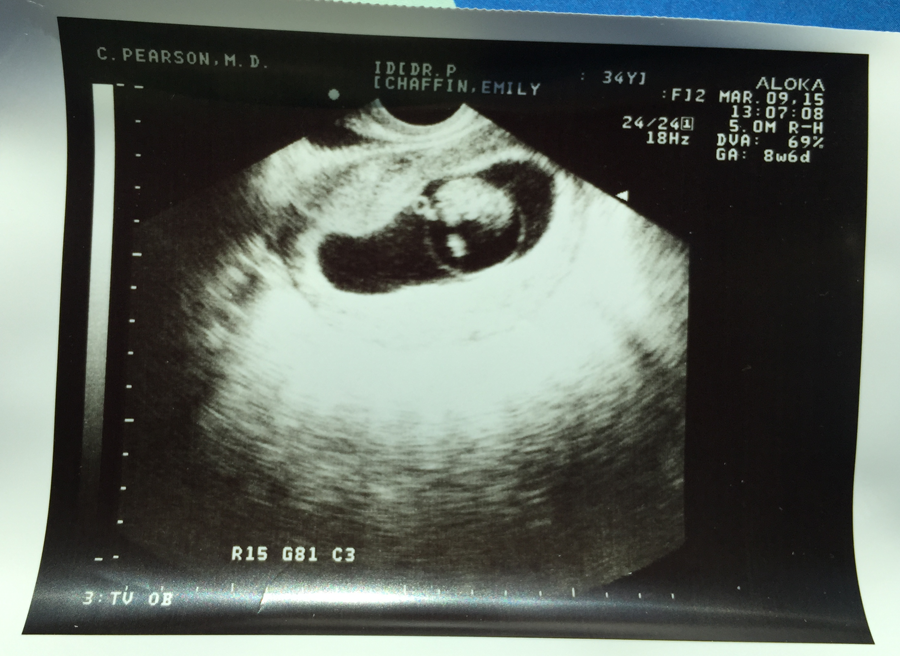

It's really hard to believe, when I stop and think about it, that I've been pregnant for most of 2015. Below is our first ultrasound, about 9 weeks. I don't know what I expected to see, but I thought it would be a little more decipherable than this! I'm still not 100% sure what I'm looking at, but I'll never forget the excited look on Justin's face when he saw it. I was excitd, too, but at the time I was getting a rather uncomfortable ultrasound, so I didn't have the luxury of watching the screen without random tools shoved in my body.

But Justin was adorable. The heartbeat flashed on the screen, and his face just lit up.